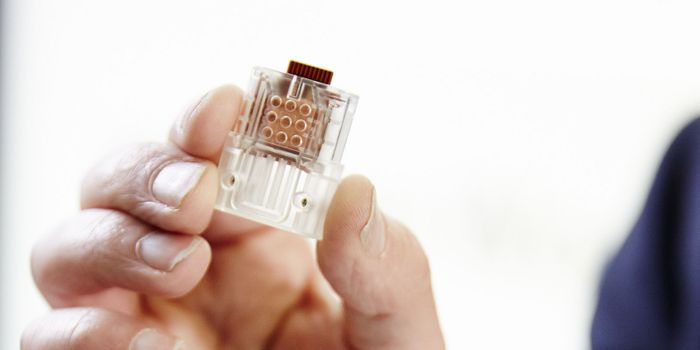

APR 16, 2016Clinical & Molecular DXMIT researchers recently engineered a flexible polymer implant that can directly release chemotherapy drugs to pancreati ...